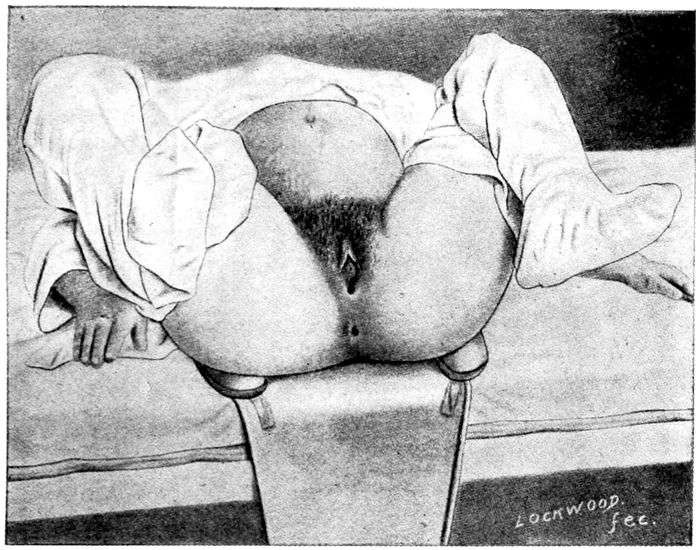

Exaggerated lithotomy position |

181 |

Dorsal position when assistants are available |

182 |